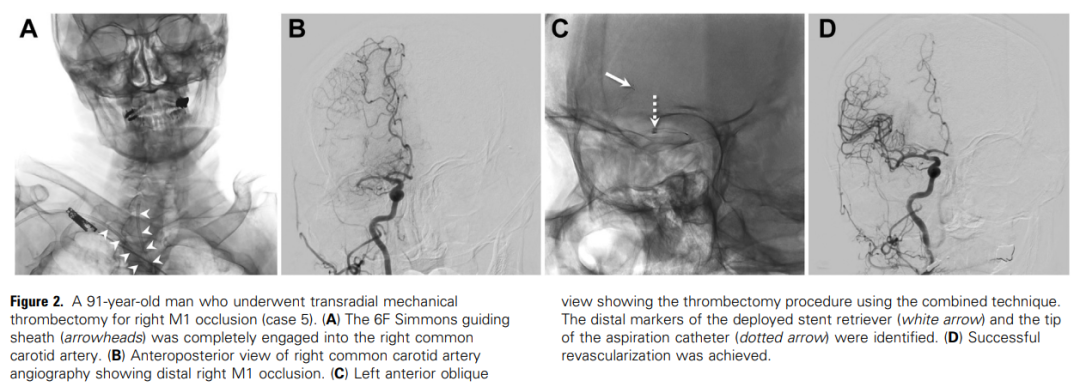

13例患者中,12例最终获得mTICI 2b,9例最终获得mTICI 2c。13例患者术中导管系统均维持稳定,无系统疝入主动脉弓,未放弃TRA或改为TFA。13例手术均获成功。共有12例患者完成90 d随访。8例预后良好(mRS评分为0-2), 4例mRS评分为3 ~ 5分。1例患者因胃穿孔死亡(mRS评分6分),与血管内取栓术无关。无手术相关并发症和血管入路部位并发症,无RAO发生。图2显示了一个说明性病例(病例5)。

图2。一名91岁男性因右侧M1闭塞接受了经桡动脉机械血栓切除术(病例5)。(A) 6F Simmons导管鞘(箭头)完全插入右侧颈总动脉。(B)右侧颈总动脉血管造影正位图显示右侧M1远端闭塞。(C)左前斜视图显示使用联合技术进行血栓切除术。可识别出已打开的取栓支架的远端标记物(白色箭头)和抽吸导管的头端(虚线箭头)。(D)成功实现血运重建。